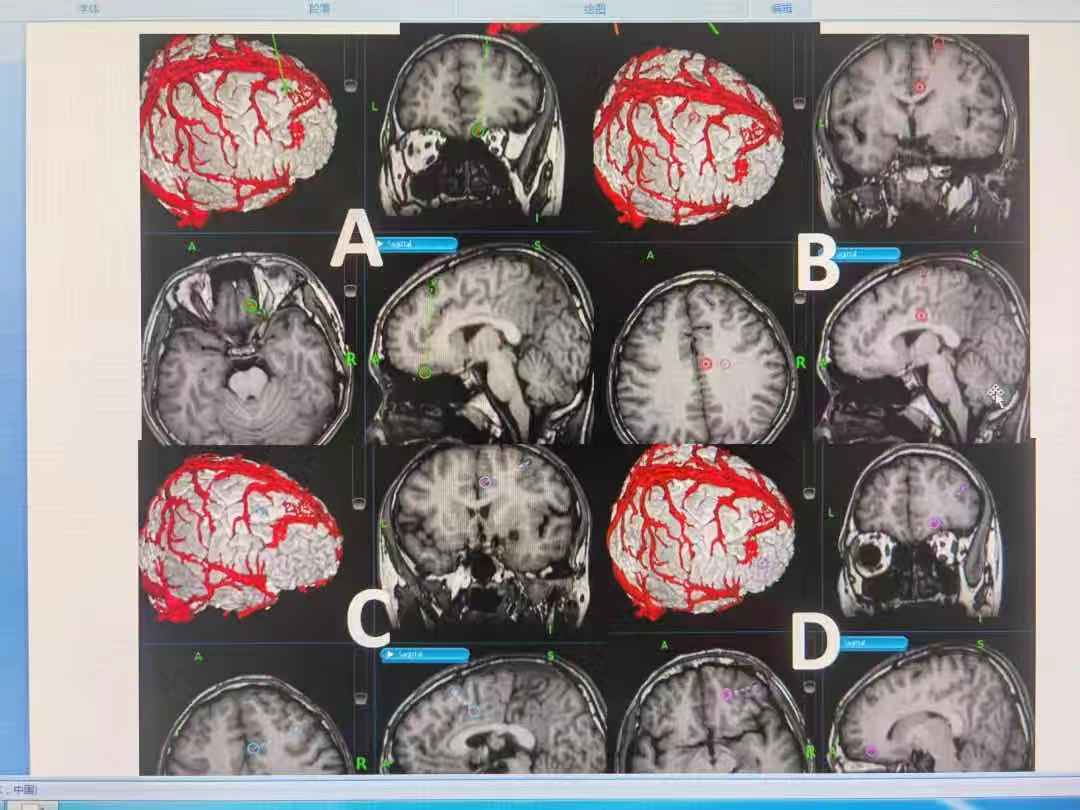

刘仕勇教授指出,难治性癫痫的外科治疗,通常包括手术切除病灶、迷走神经电刺激术以及SEEG引导下射频热凝毁损。目前外科手术切除癫痫病灶仍然是治疗难治性癫痫的首选方式。专家强调指出,要想将癫痫治愈就需要把异常放电的癫痫灶找到并切除掉,而目前常用的皮层脑电图只能从一个表面推测病变部位,无法精准监测到病灶位置,此外,脑部神经错综复杂一旦伤及其他神经元,后果不堪设想,而先进的立体定向脑电图技术(SEEG)能很好避开脑血管及重要脑功能区,通过微创外科手术,将电极放入大脑深部,全面监测癫痫的起源、扩散和症状产生,构建3D的“癫痫网络”,为癫痫外科手术提供更加精准、立体、完整的定位。

在经过全面的检查和详细了解孩子的病史后,专家决定为其进行SEEG检查。检查中,专家通过磁导航和术中脑电图引导,根据癫痫病灶的提示经皮精准插入9根电极针,通过这9根电极针对王鑫的癫痫病灶进行精准的3D定位,从而为毁损病灶提供更加精准的指引。